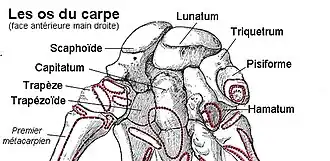

L'os scaphoïde (du grec ancien σκαφοειδής « qui ressemble à un bateau allongé[1] ») ou anciennement os naviculaire carpien, est un os de la première rangée du carpe dont le rôle fonctionnel (avec le lunatum) est fondamental dans la biomécanique du poignet.

Le scaphoïde est l'os le plus latéral (ou externe) et le plus volumineux de la rangée proximale (ou supérieure) du carpe. Il a une forme un peu allongée, dirigée vers le bas, le côté latéral et un peu en avant.

Sa face supérieure est une surface articulaire convexe et regarde en haut et latéralement. Elle s'articule avec le radius au sein de l'articulation radio-carpienne.

Sa face médiale est articulaire avec l'os lunatum.

Son bord médial présente une surface articulaire concave orientée médialement et en bas avec la tête de l'os capitatum.

Sa face inférieure est convexe. Elle présente deux facettes articulaires quadrilatères séparées par une crête arrondie.La facette latérale s'articule avec l'os trapèze et la facette médiale avec l'os trapézoïde.